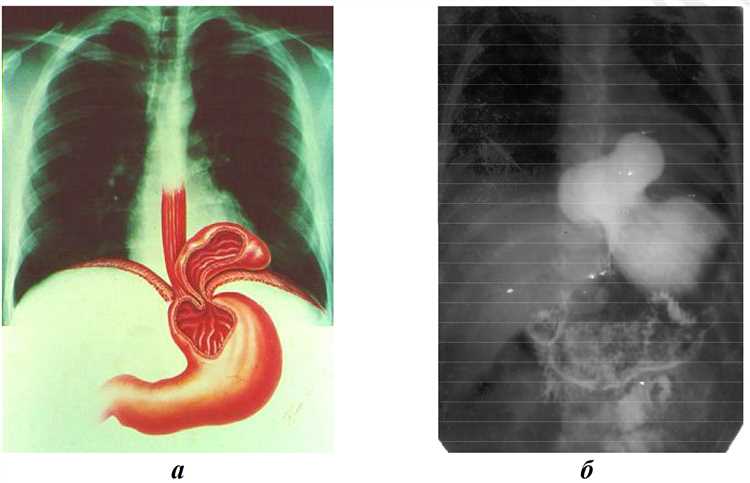

Технические аспекты рентгенографии грыжи

Рентгенографические исследования играют важную роль в обнаружении аномалий в области, подверженной образованию грыжевых выпячиваний. Эти подходы позволяют визуализировать структуру организма и выявить возможные нарушения. Качество изображений напрямую зависит от различных факторов, начиная от применения специального оборудования и заканчивая качеством исполнения процедур.

Основным компонентом рентгенографии является рентгеновский аппарат, который производит ионизирующее излучение. Это излучение проходит через исследуемую область и фиксируется на фоточувствительной пленке или цифровом детекторе. Важно учитывать параметры, такие как энергия излучения и время экспозиции, так как они оказывают значительное влияние на четкость получаемых изображений.

Технические аспекты процедуры также включают выбор правильного положения пациента, поскольку это позволяет оптимально отобразить область исследования. Позиционирование может варьироваться в зависимости от типа предполагаемой патологии. Кроме того, использование контрастных веществ может помочь в выделении определенных структур и улучшении качества снимков.

Другим важным аспектом является обработка и интерпретация рентгенограммы. Этот процесс требует специализированного подхода от медицинского работника, потому что необходимо учитывать не только очевидные изменения, но и более тонкие детали, которые могут свидетельствовать о наличии патологии. Поэтому контроль за качеством изображений и грамотная диагностика являются неотъемлемыми частями успешного процесса исследования.